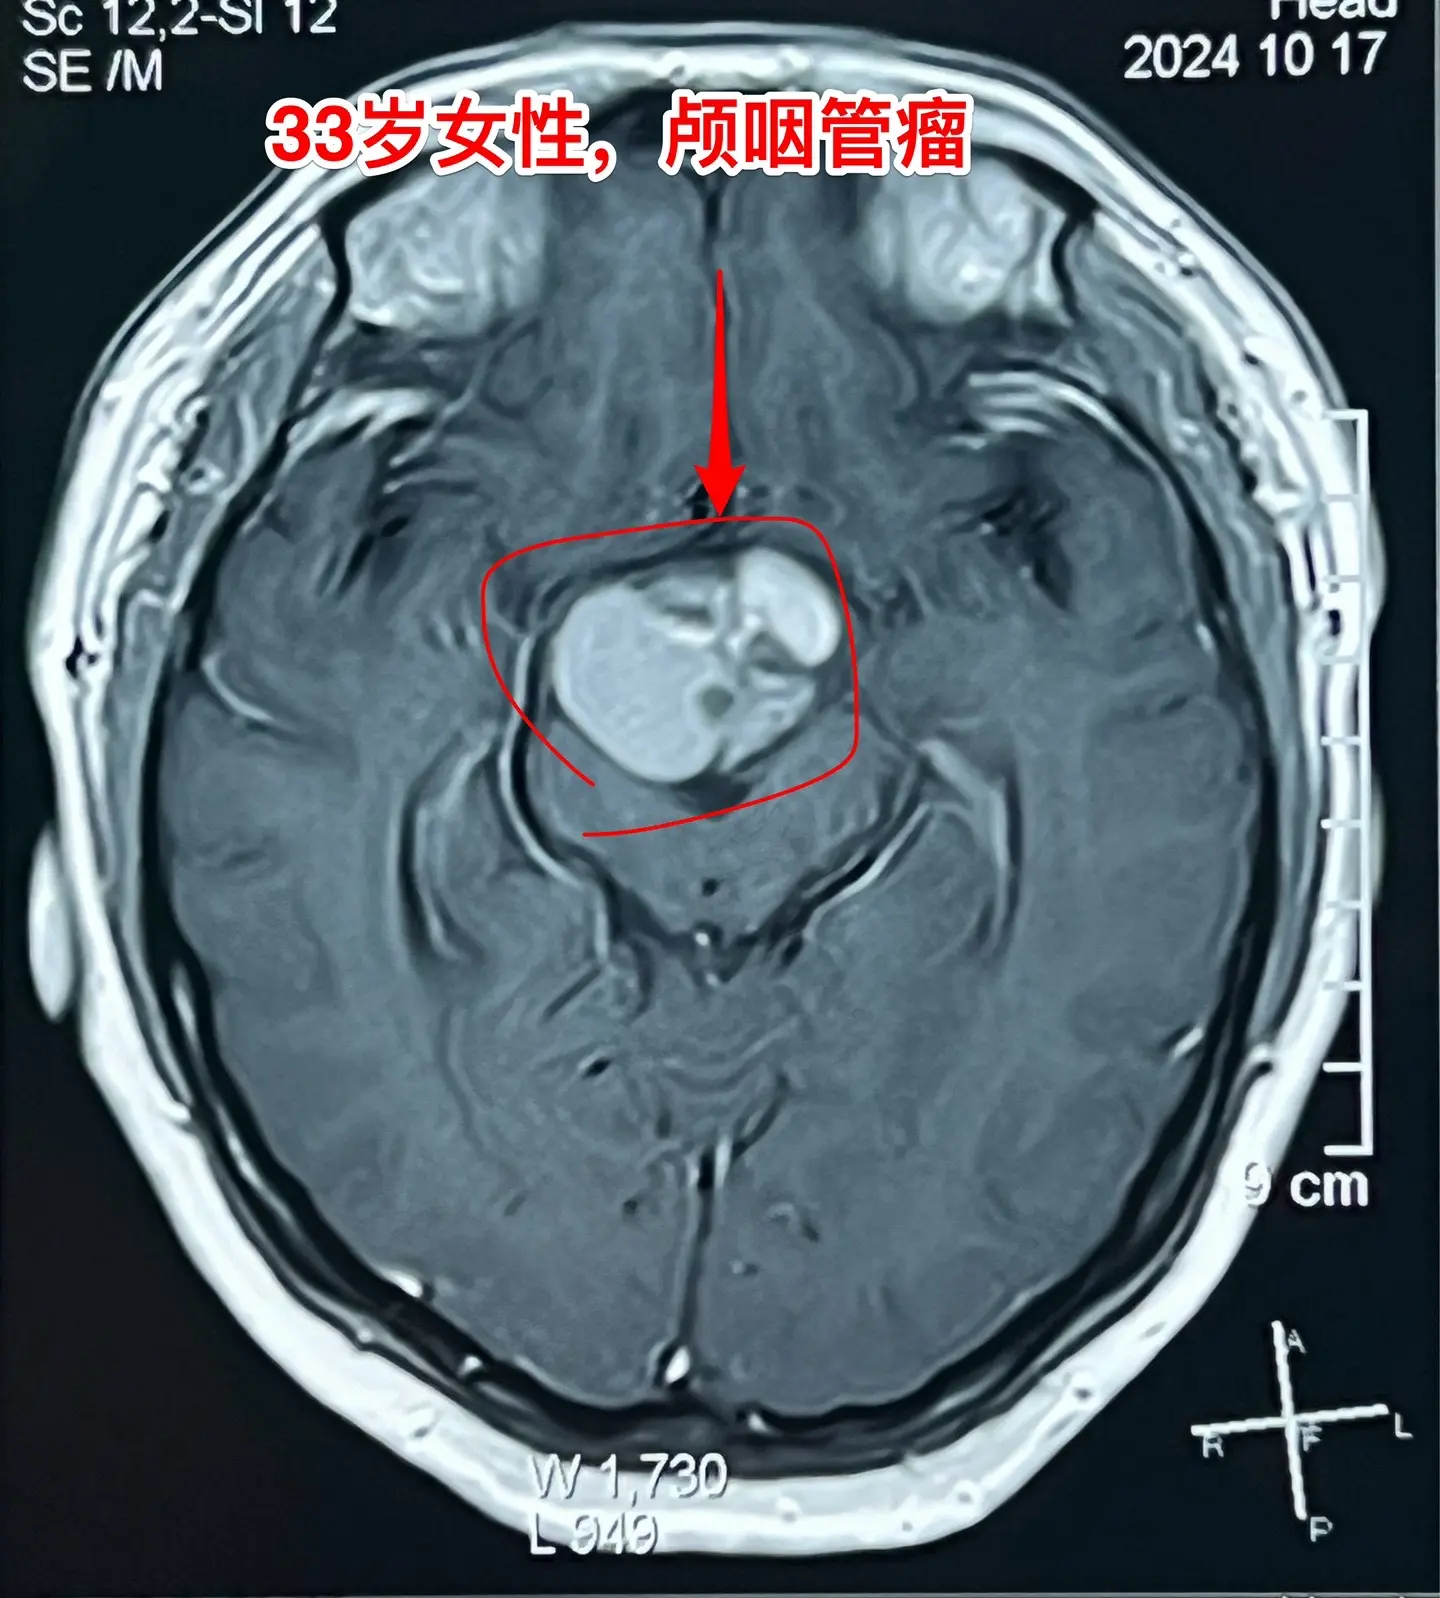

33岁颅咽管瘤患者终于下决心作手术了。洛阳市的女教师,2021年因内分泌紊乱到医院检查,就发现了颅咽管瘤。 由于对手术感到恐惧,再加上工作原因和其他原因,患者一直在观察中,未作手术。 她认识好几个曾经在我这里作过手术的颅咽管瘤病友,每一个成功的手术对她都是一次鼓励! 今年八月份患者和我联系了,说磁共振显示肿瘤在增大,有脑积水了,她也有多睡症状,视力有下降。所以她下定决心要来作手术。 10.28行开颅手术将肿瘤完全切除。肿瘤内有大块钙化,将肿瘤完全切除。手术后患者自述视力有好转。